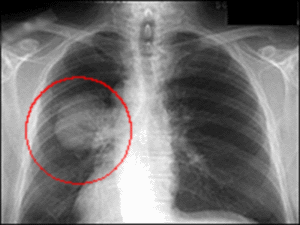

Рак легких – один из самых распространенных видов этого заболевания. В чем тут причина: загрязнение воздуха, распространенность курения или что-то иное, – доподлинно неизвестно. Одно можно сказать точно: болезнь эта лечится с трудом, но шансы все-таки есть.

Ранняя диагностика – главный фактор успеха!

Если вы живете не в самом благополучном в экологическом отношении регионе, если не можете избавиться от курения или работаете на вредном производстве, – важно регулярно проходить тщательный осмотр и сдавать анализы, которые позволили бы выявить раковые клетки при их наличии.

Учтите: операция на легких при раке возможна лишь на ранней стадии его развития. На более поздних, когда метастазы уже распространились на соседние органы, это часто бессмысленно. Поэтому, если вас что-то беспокоит, лучше пройти диагностику. При лечении на ранней стадии любая злокачественная опухоль может быть ликвидирована без серьезных последствий.